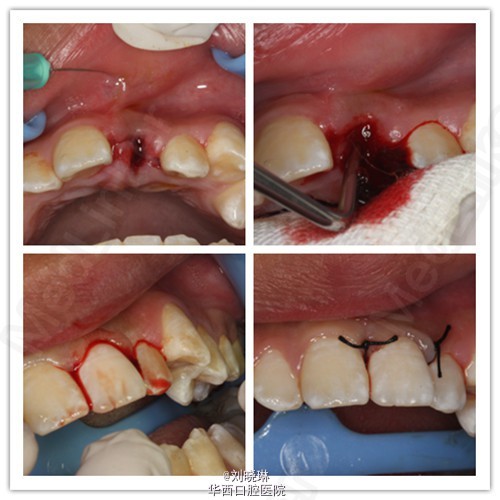

病人14岁,外伤导致上前牙脱落,患牙离体时间超过30小时。给患者讲明离体时间过长,患牙又未做正确方式保存,再植成功率低,患者要求试保留再植,术前签知情同意书。